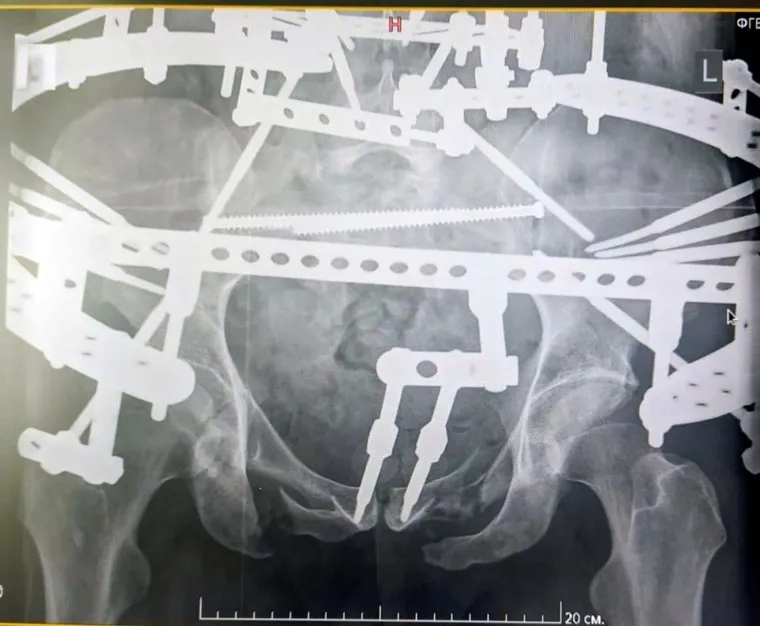

В курганском Центре им. Илизарова прооперировали пациента со сложной травмой таза и позвоночника, возникшей из-за падения с большой высоты. Сразу после травмы молодой человек потерял подвижность, но благодаря реконструкции таза он начал садиться и вставать, сообщили в пресс-службе медицинского центра.

«Экстраординарный клинический случай в практике врачей Центра Илизарова. В клинику реконструктивной хирургии повреждений конечностей и таза поступил 24-летний пациент из г. Тобольска, у которого таз был оторван от позвоночника. Пациенту провели сложное многоэтапное хирургическое вмешательство по реконструкции тазового кольца и крестцового отдела позвоночника. Выполнили надежную фиксацию позвоночника и таза. Операция шла около 6 часов», — говорится в сообщении Центра Илизарова.

Молодой человек упал с 4-го этажа своего дома в Тобольске. После травмы таз и тело пациента между собой были связаны только мышцами, он не мог двигаться. В больнице Тобольска ему провели первичную стабилизацию костей таза и переломов ног аппаратами внешней фиксации. Учитывая сложность травмы, мужчину направили в курганский медцентр. Как только курганские врачи связали таз с позвоночником, мышцы заработали, парень начал поворачиваться, садиться и даже вставать. Сейчас пациент находится под наблюдением, врачи дают хорошие прогнозы на восстановление.